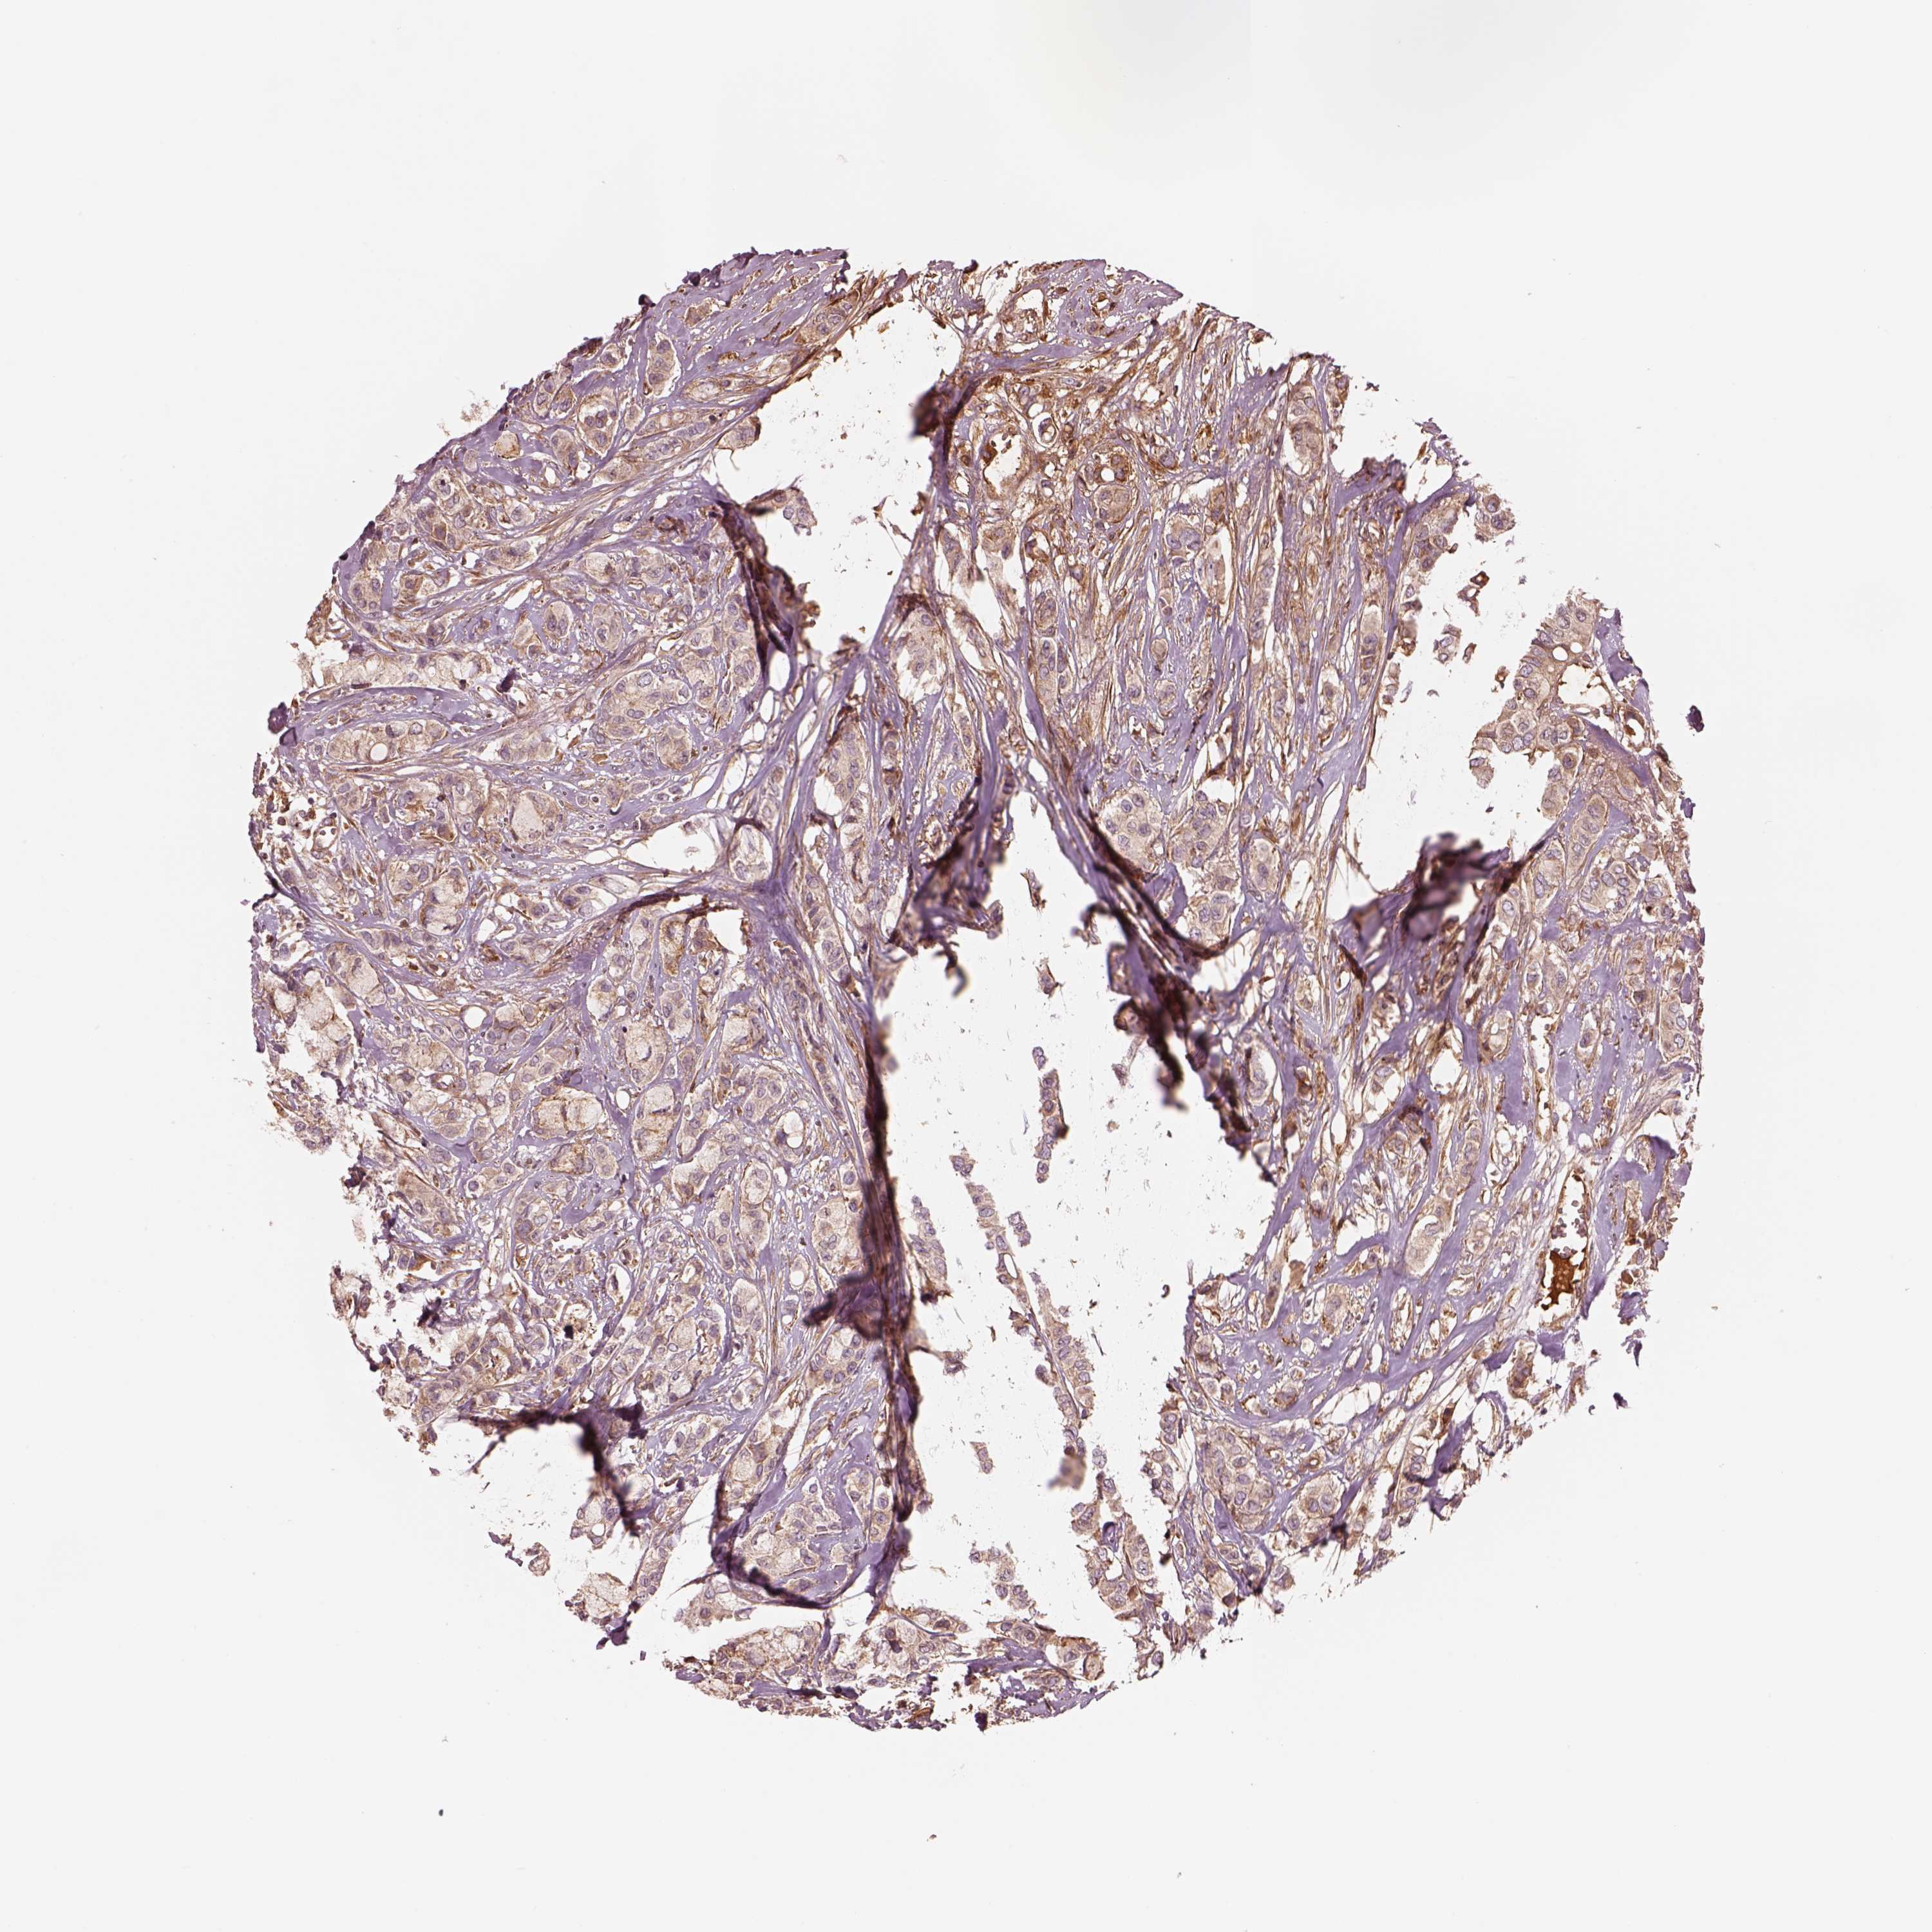

CANCER BREAST CANCER Show tissue menu

BRCA TCGA BRCA VALIDATION PROTEIN EXPRESSION